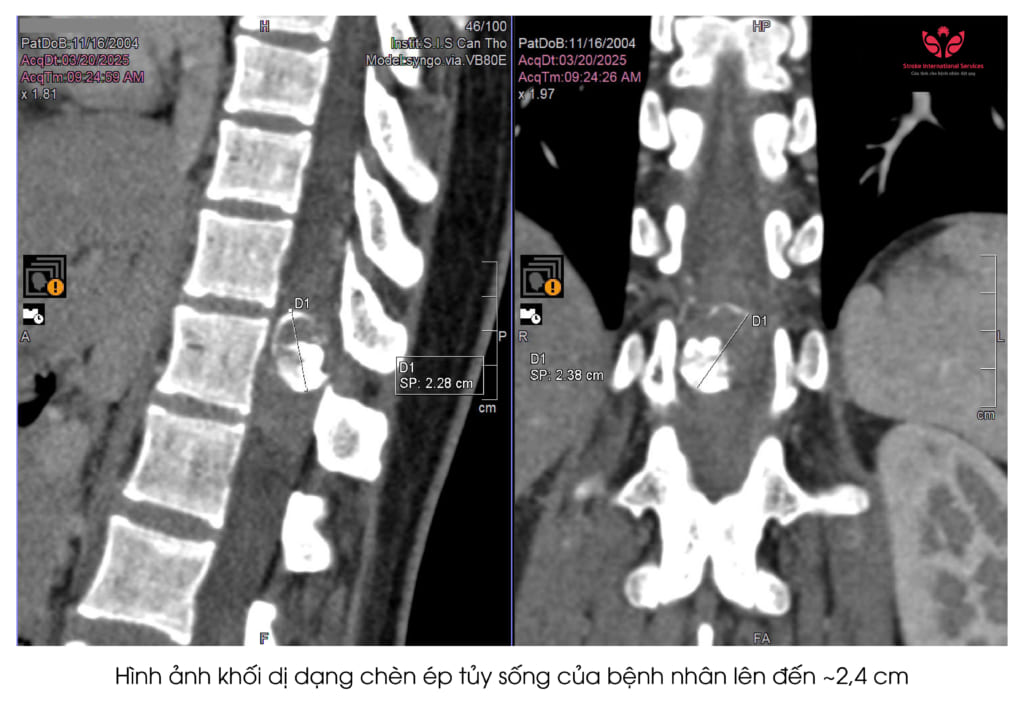

“Khi bệnh nhân đến khám, từ các triệu chứng điển hình các bác sĩ nghi ngờ có dấu hiệu tổn thương hệ thần kinh tủy sống và chỉ định cho bệnh nhân chụp cộng hưởng từ cột sống. Kết quả hình ảnh học cho thấy khối dị dạng lớn ở vùng mạch máu tủy. Khối dị dạng này gây phù tủy, chèn ép rất nặng gây yếu chân. Thông thường đường kính tủy sống khoảng 2 cm. Nhưng túi phình dị dạng có đường kính lên đến 2,4 cm đã chèn ép toàn bộ vùng chóp cùng tủy trong đó có chùm đuôi ngựa.

Rất may mắn bệnh nhân đã được tiến hành điều trị kịp thời. Ê kíp bác sĩ đã tiến hành hội chẩn và có chỉ định điều trị can thiệp gây tắc mạch máu. Sau khi gây tắc chỗ thông động tĩnh mạch tủy đã được chữa khỏi hoàn toàn. Túi phình có kích thước rất lớn nên cần phải mổ cắt bỏ hoàn toàn vùng dị dạng. Như vậy mới có cơ hội phục hồi cho bệnh nhân.